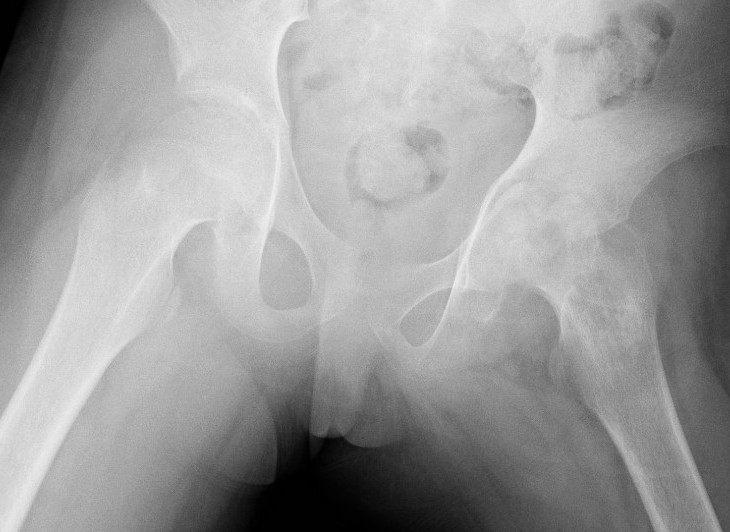

Complications

AVN

Chondrolysis

Physeal arrest

Subluxation / dislocation

Septic arthritisSeptic arthritis

Advanced AVN and collapse after hip septic arthritis

Paed Hip OMPaed OM